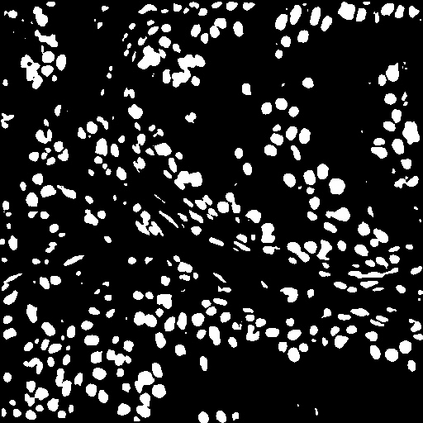

Due to the limitation of available labeled data, medical image segmentation is a challenging task for deep learning. Traditional data augmentation techniques have been shown to improve segmentation network performances by optimizing the usage of few training examples. However, current augmentation approaches for segmentation do not tackle the strong texture bias of convolutional neural networks, observed in several studies. This work shows on the MoNuSeg dataset that style augmentation, which is already used in classification tasks, helps reducing texture over-fitting and improves segmentation performance.

翻译:由于现有标签数据有限,医学图像分割是深层学习的一项艰巨任务,传统数据增强技术已证明通过优化使用少数培训实例来改善分割网络的性能,但是,目前的分割增强方法没有解决若干研究中观察到的动态神经网络的强烈纹理偏差问题。 这项工作显示在MONUSeg数据集中已经用于分类任务的样式增强,有助于减少纹理的过度装配,改善分割性能。